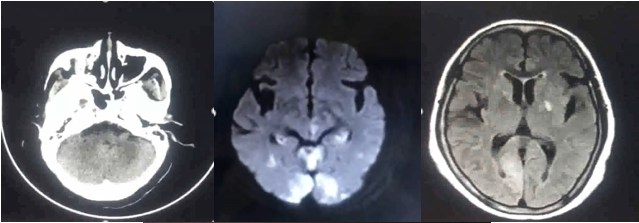

影像诊断

病历夹什么径技·第151期|串联营病历夹:京广连营_https://www.jmylbn.com_新闻资讯_第72张

病历夹什么径技·第151期|串联营病历夹:京广连营_https://www.jmylbn.com_新闻资讯_第73张

病历夹什么径技·第151期|串联营病历夹:京广连营_https://www.jmylbn.com_新闻资讯_第74张

<<滑动查看下一张图片>>

结论:颅脑CT提示左侧基底节、放射冠区腔隙样软化灶。颅脑DWI提示双侧小脑、桥脑、中脑、双侧海马、双侧枕叶、右侧丘脑及右侧胼胝体多发急性脑梗塞。颅脑MRA提示基底动脉及双侧大脑后动脉未见显示;右侧大脑中动脉中-重度狭窄;脑动脉硬化。初步诊断为急性后循环脑梗死,基底动脉闭塞。